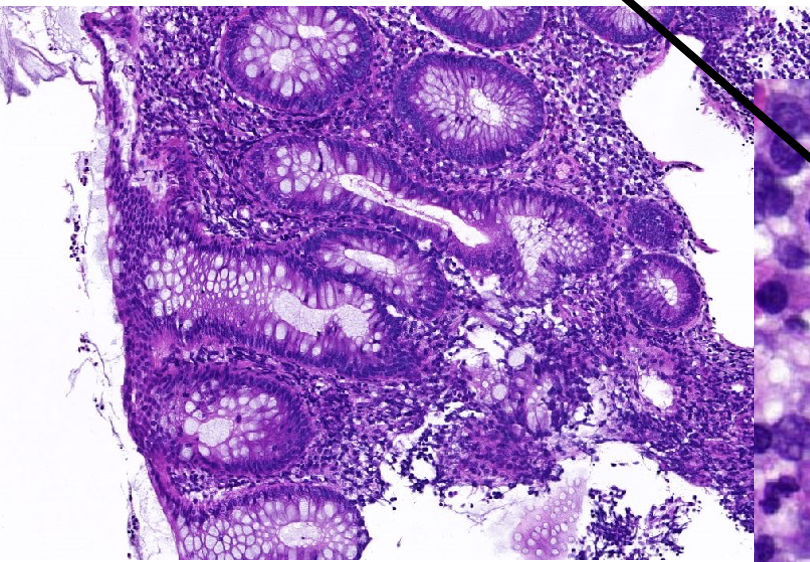

welk orgaan

appendix

lagen van mucosa v appendix (buiten naar binnen)

eenlagig cilindrisch epitheel

lamina prompria met lymfefollikels

muscularis mucosa

hoe noemt men bij appendicitis het ding waarmee het lumen gevuld is+ welke cellen

purulent exsudaat

neutrofiele granulocyten

plasmacellen

lymfocyten

wat toont pathologisch aan dat het gaat over appendicitis en geen andere ontsteking

erosie: onderbreking epitheel

ulceratie: diepere onderbreking + mucose met granulocyten

inflammatie in alle lagen (niet enkel in lumen)

welke inflammatoire cellen aanwezig bij appendicitis